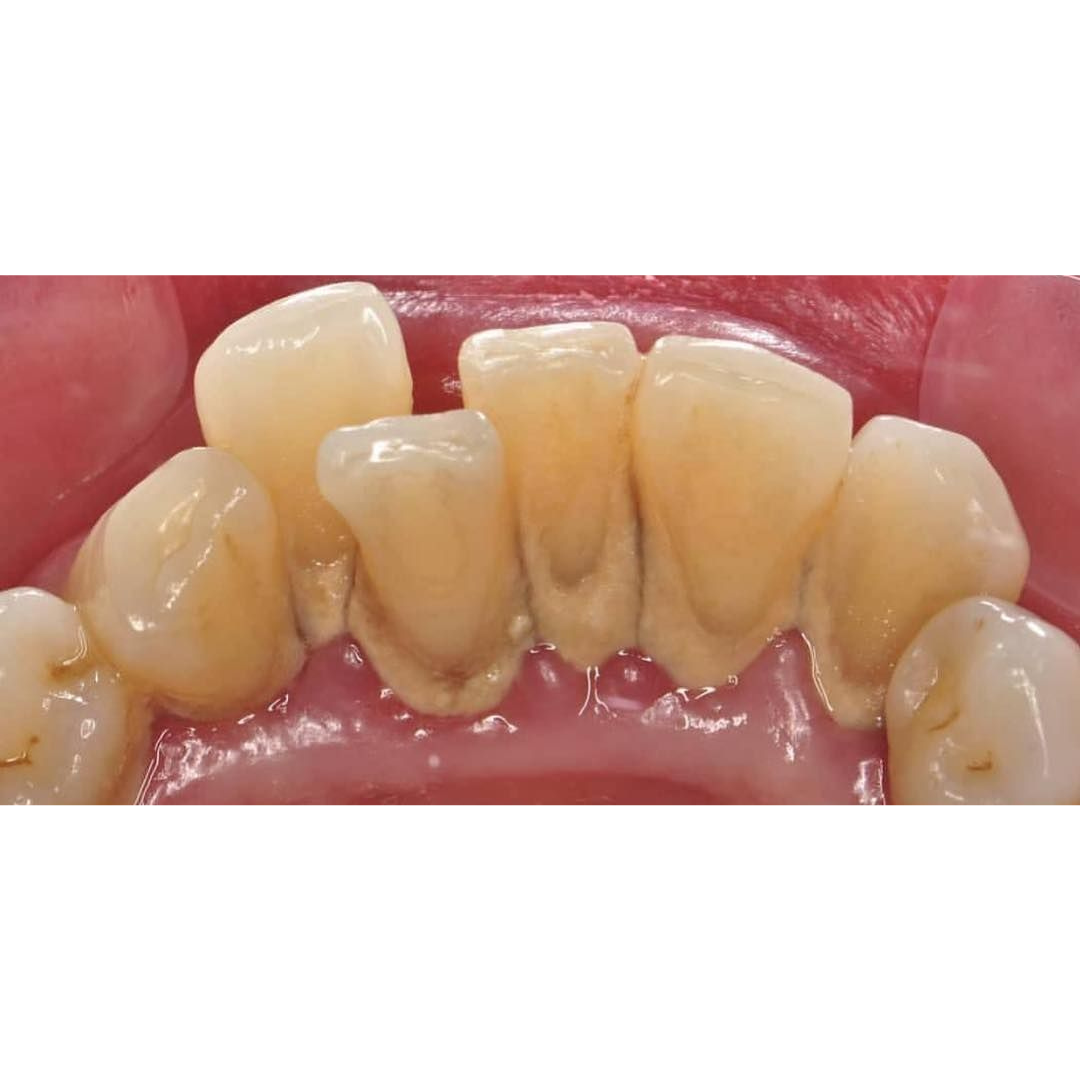

Before & After

📸 Before & After: Scaling Results

From Dental Fear to a Confident Smile

Scaling for Teeth or Dental Scaling (teeth cleaning) is a fundamental preventive dental treatment designed to remove plaque and hardened tartar (calculus) from the surface of teeth and along the gumline. Tartar forms when plaque hardens due to minerals in saliva, and it cannot be removed by brushing alone.

If left untreated, tartar buildup can cause bleeding gums, swollen gums, bad breath, and gum disease (periodontitis), which may eventually lead to loose or lost teeth.